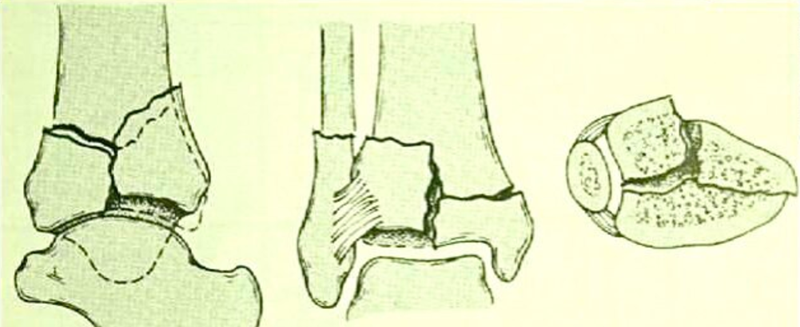

图5 Ⅲ型:严重的关节面粉碎和干骺端嵌压的移位骨折

诊断:左胫骨平台后柱骨折,后交叉韧带撕脱骨折,左踝关节pilon骨折3型。

图8 Pilon骨折3型